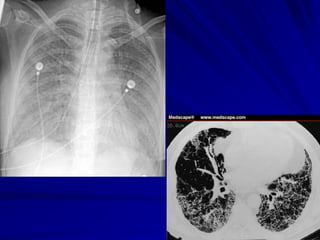

VP điển hình: diễn tiến cấp tính với sốt cao, rét

run, đau ngực, ho có đàm. Xquang phổi: có

hình ảnh VP thuỳ. Điển hình: VP do phế cầu.

VP không điển hình: khởi phát từ từ (nhiều

ngày, vài tuần), sốt nhẹ, ho khan, nhức đầu,

mệt mõi. Xquang phổi không có hình ảnh VP

thuỳ điển hình, nhuộm gram đàm âm tính, kém

đáp ứng với điều trị kháng sinh họ penicillin.

X QUANG PHỔI

Heulitt (1988): Xquang có:

Độ nhạy cảm: 45 %

Độ đặc hiệu: 92 %

X quang: dấu hiệu chỉ điểm kém cho

nguyên nhân VP

• Không có hình ảnh Xquang đặc hiệu

cho VP do virus, TN không điển hình

• Không thể giúp phân biệt VP do VT

hay do virus

• VP thùy/Xquang: giá trị cao cho VP vi

trùng nếu kèm sốt cao (39oC), BC tăng

(>20.000/mm3) (Spec=74%)

Chụp Xquang ngực cắt lớp (CT)

Niều lợi điểm hơn Xquang quy ước trong

đánh giá tổn thương nhu mô phổi và phân

biệt với các bất thường trong lồng ngực

khác đặc biệt khi có thể có nhiều hình ảnh

tổn thương chồng lên nhau, tổn thương

lan rộng nhiều vị trí giải phẩu (nhu mô

phổi, màng phổi, trung thất).

Chỉ chỉ định CT ngực khi cần chẩn đoán

phân biệt, đánh giá biến chứng.